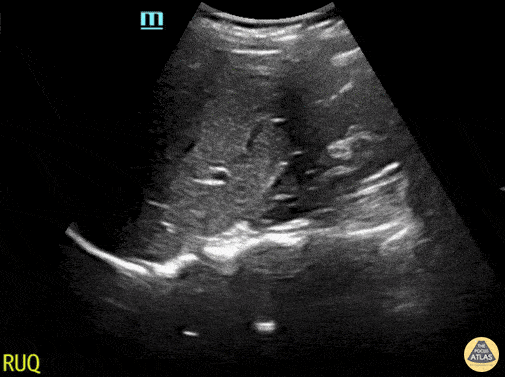

Normal RUQ ultrasound. Contributor: Maher M. Abulfaraj, MD, @mahermabulfaraj

View: Unspecified Parasternal Long Axis Parasternal Short Axis Apical Four-Chamber Subcostal Four-Chamber Subcostal Inferior Vena Cava Right Upper Quadrant Left Upper Quadrant Suprapubic Longitudinal Suprapubic Transverse Subxiphoid Anterior Thoracic Phrenic